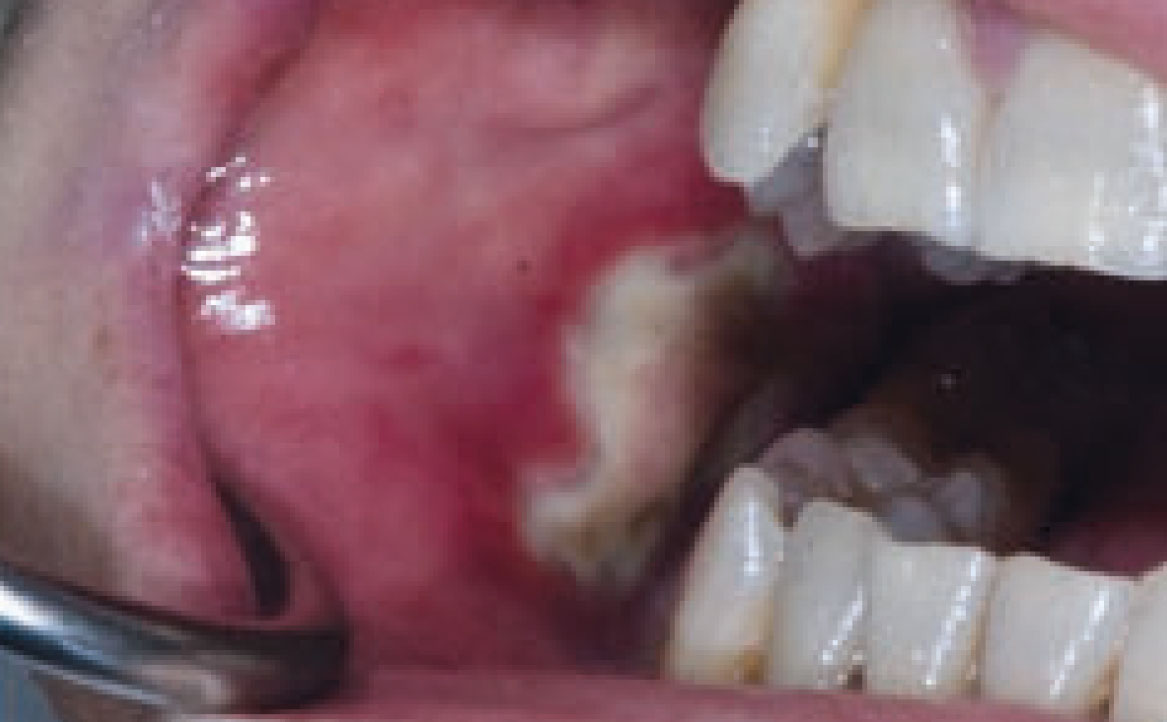

Le lesioni orali caratteristiche del lupus eritematoso mostrano una somiglianza clinica con le manifestazioni del lichen planus orale, presentando zone irregolari di atrofia/erosioni o ulcerazioni, circondate da lesioni reticolari ipercheratosiche. Queste lesioni sono solitamente localizzate principalmente nel palato, nella mucosa geniena, nella mucosa alveolare o gengivale (fig. 4). Dato che il coinvolgimento del palato è poco comune nel lichen planus, la sua presenza potrebbe agevolare la diagnosi differenziale. Nel caso del LE indotto da farmaci, si osserva un miglioramento delle lesioni entro alcuni giorni o settimane dalla sospensione del farmaco causante. Tra i farmaci più frequentemente coinvolti si annoverano l’idralazina e la procainamide (20%) (20). Altri farmaci potenzialmente correlati al LE includono i β-bloccanti, le sulfonamidi, l’isoniazide, la clorpromazina, la metildopa, la penicillamina, la chinidina e gli agenti biologici come gli inibitori anti-TNF (21).